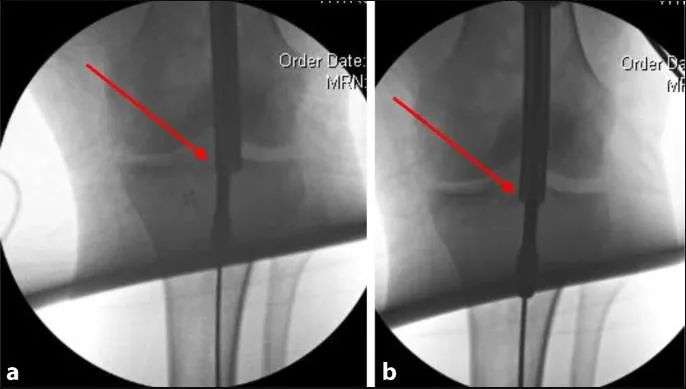

Anu ngabalukarkeun utama malalignment dina fractures tibial proksimal nyaéta deformity disababkeun ku narik tina urat quadriceps salila flexion dengkul jeung konflik mékanis antara ujung kuku jeung cortex tibial posterior salila sisipan susuk. Patella ogé nyegah asupna axial tina paku dina pesawat sagittal (Gbr. 1a, b). Ku alatan éta, métode umum sejen nuliskeun titik ngaliwatan incision parapatellar medial, nu ngakibatkeun sisipan kuku rada medial-to-lateral (Gbr. 1c jeung 2). Nalika kuku asup kana kanal intramedullary distal ka narekahan, bagian proksimal dimiringkeun kana hiji exostosis (Gbr. 2). Tungtungna, tegangan istirahat tina otot chamber anterior nyumbang rada ka ectropion nu (Gbr. 3).

Gambar 1 a,b Ngagunakeun pendekatan infrapatellar konvensional, patella nu nyegah asupna axial tina paku, hasilna deformity umum anterior apical alignment sagittal na ectropion coronal alignment.c Intramedullary alignment kuku dipigawé ngagunakeun pendekatan parapatellar.